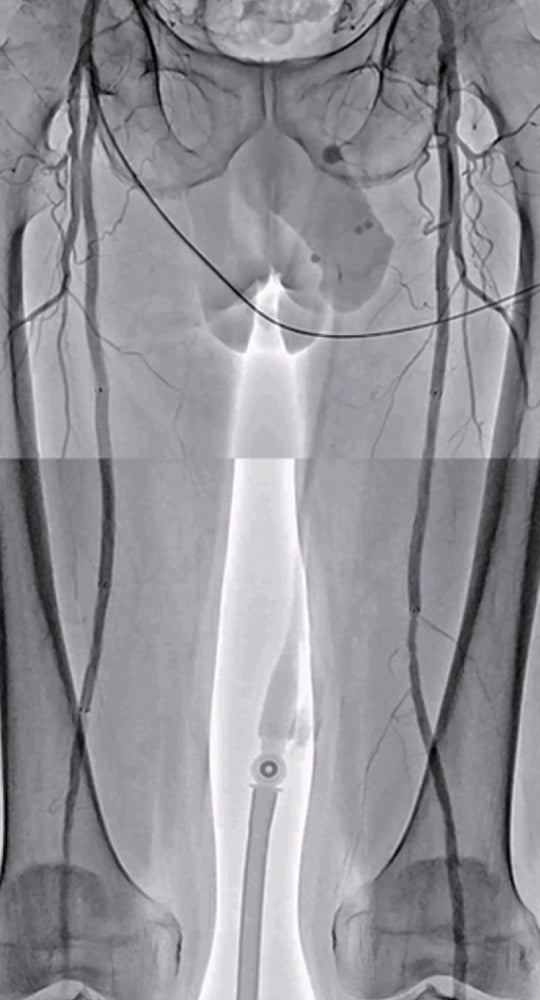

左浅大腿動脈閉塞(図1):右鼠径部を穿刺(6 Frシース)しcrossover後、順行性に0.014 inchマイクロカテーテルを使用して0.014 inchガイドワイヤー(先端荷重1 g→40 g)を進め貫通、IVUS catheterで真腔を捕らえていることを確認。5.0 mm径バルーン(non-compliant balloon)で拡張後解離が生じ、末梢にバイアバーン® ステントグラフト5.0 × 150 mm、中枢に6.0 × 150 mmの2本を留置。病変の末梢には発達した1本の側副血行路を伴い、側副血行路の中枢側に健常部位があったため、側副血行路をjailせずバイアバーン® ステントグラフトを留置。5.0 mm径と6.0 mm径バルーン(non-compliant balloon)で後拡張して終了。(図2)

右浅大腿動脈閉塞(図3): 左鼠径部を穿刺(6 Fr シース)しcrossover後、順行性に0.014 inchマイクロカテーテルを使用して0.014 inch ガイドワイヤー(先端荷重1 g →3 g →40 g)を進めたが貫通できず、足背動脈を穿刺し逆行性に0.014 inch ガイドワイヤーを進め、貫通に成功。IVUS catheterで一部 subintimal trackingしていることを確認。5.0 mm 径バルーン(non-compliant balloon)で拡張後解離が生じ、末梢にバイアバーン® ステントグラフト5.0 × 150 mm、中枢に6.0 × 250 mm の2本を留置。病変の末梢には発達した2本の側副血行路を伴い、側副血行路の間に軽度狭窄病変を認めたため、中枢側の側副血行路をjailさせ、健常部にバイアバーン® ステントグラフトを留置。5.0 mm 径と6.0 mm 径バルーン(non-compliant balloon)で後拡張して終了。(図4)